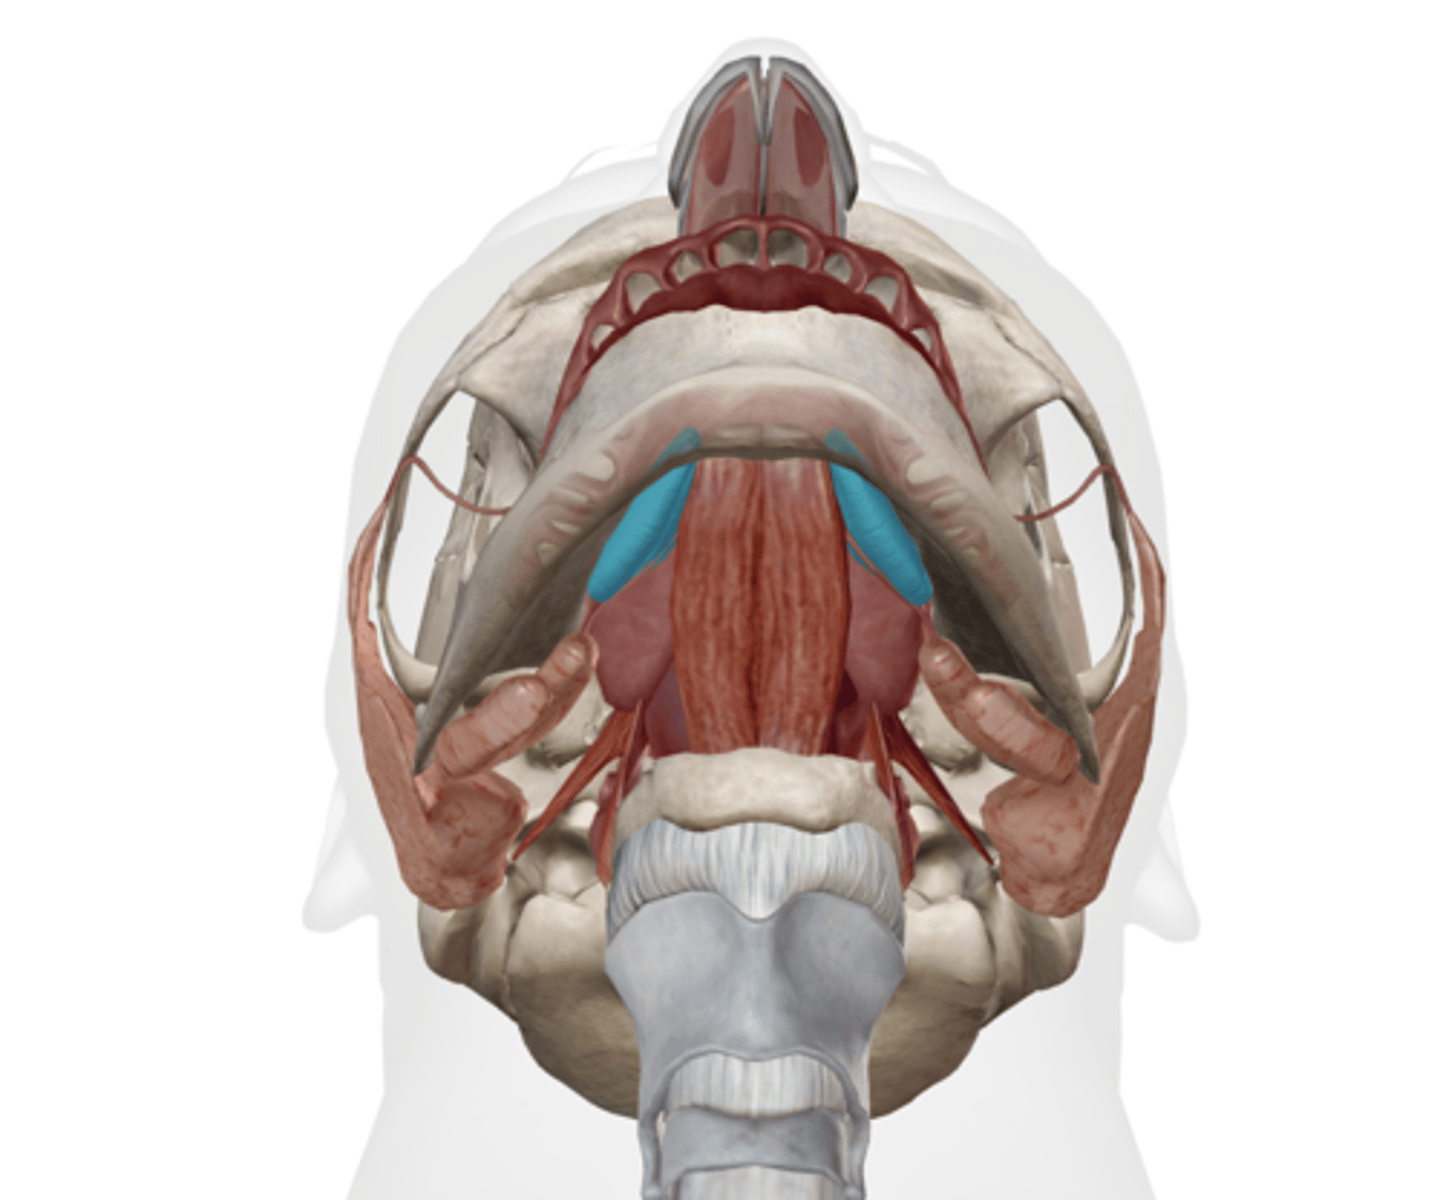

Submandibular duct

Sublingual gland